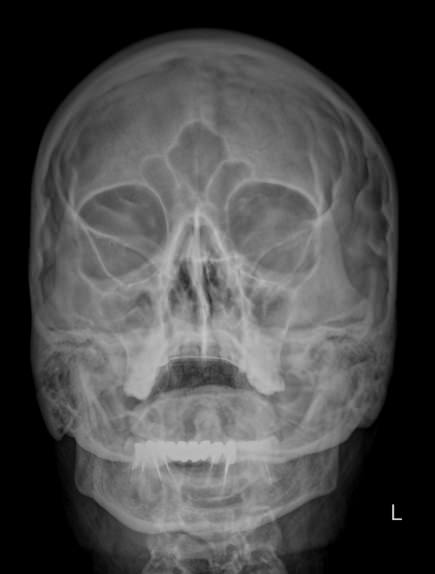

Предпочтительным методом диагностики искривления носовой перегородки является рентгенография. Это безболезненный, доступный и безопасный способ подтвердить искривление и определить его степень. Цифровая аппаратура последнего поколения испускает минимальную дозу излучения, сравнимую с естественным фоном.

Что покажет рентген костей носа при искривлении носовой перегородки

• Утолщение носовой перегородки;

• Искривление хрящевой части;

• Перелом костной части, в том числе со смещением;

• Новообразование, сдвигающее или разрушающее перегородку;

• Костные разрастания на прямой перегородке;

• Отек и воспаление мягких тканей.